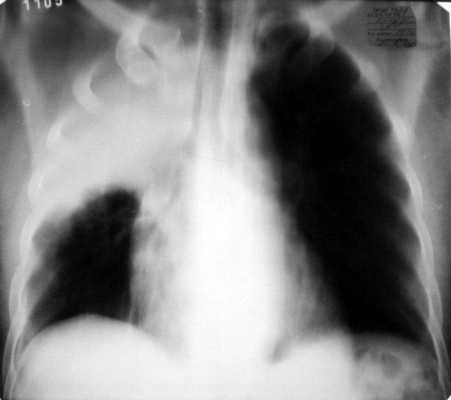

Томография. Данная методика является следующим этапом в рентгенологическом обследовании (рис. 3.3). Чаще используется продольная прямая томография. Срединный срез производится на уровне половины толщины грудной клетки; середина передне-заднего диаметра (от спины к грудине) у взрослого равна 9-12 см.

Рис. 3.3. Продольная томограмма грудной клетки на уровне бифуркации трахеи. Правая верхняя доля уменьшена в размерах, интенсивно гомогенно затемнена. Нижняя граница затемнения вогнута. Средостение смещено вправо. Просвет правого верхнедолевого бронха не визуализируется. Обтурационный ателектаз верхней доли правого легкого.

Передний срез находится на 2 см ближе от срединного кпереди, и задний срез − на 2 см кзади от срединного. На срединной томограмме не будут выявляться тени ни передних, ни задних отделов ребер, на передней томограмме хорошо визуализируются передние отделы ребер, а на задней томограмме, наоборот, задние отделы ребер. Обычно по этим основным признакам наиболее просто можно опознать топографические срезы легких. Продольная томография применяется для: